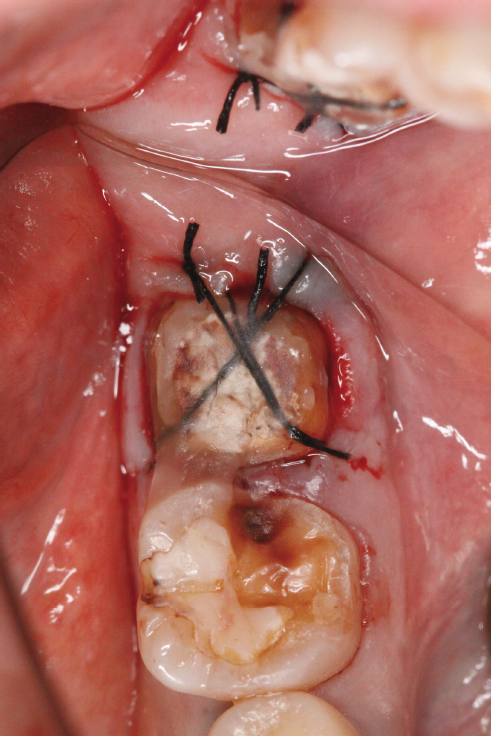

当院に来院される患者さんの多くは『他院で抜くしかないと言われる歯をなんとか残して欲しい』と言う希望の元来られます。現在歯を失う大きな原因となっている3大原因は『虫歯、歯周病、破折』です。多くは虫歯や破折なのですがこう言った歯の場合の治療には根管治療が必要になることがほとんどです。根管治療とは簡単に言うと、『ラバーダム』(写真1)と言われるゴムのカバーを歯に取り付け、根っこの中にある汚れを隅々まで取り、できる限り無菌に近い状態にして最後に蓋をする、と言う一連の流れになります。そしてその際に根っこの中にヒビが見つかったり根っこの中からのお掃除では綺麗になりきらず治癒しない場合は再植と言う治療になります。再植は『一回歯を抜いてお口の外でその歯を治療し再びお口の中に戻す』と言うものです。(写真2)『抜いた歯を再び植える』と言うことで再植と言う名がついています、他の方法で違う場所から歯を持ってきて(移動してきて)植える事を『移植』と呼んだりしてます。こちらの移植の方が臓器等、医科の分野でも使われる技術なので皆様には馴染みがあるかもしれませんね。

そしてこの再植と言う治療に入ると歯を一旦抜くことによって一時的に歯は弱まるのでしっかり休めなければなりません、期間はその歯の状態や個々の回復の差によりますが基本的には4ヶ月程休ませてあげます。その4ヶ月の間歯は噛ませることなくそっとしておくのですがその待っている間に『土台』を建てます。(写真3)この土台に関しては当会の会報誌でもまだ説明したことがないのでいずれ紹介しようと思っています。この土台の治療とは根っこの治療が終わった歯にするもので根っこに再度菌が入り込みにくくする、歯を割れにくくする、などの意味があります。